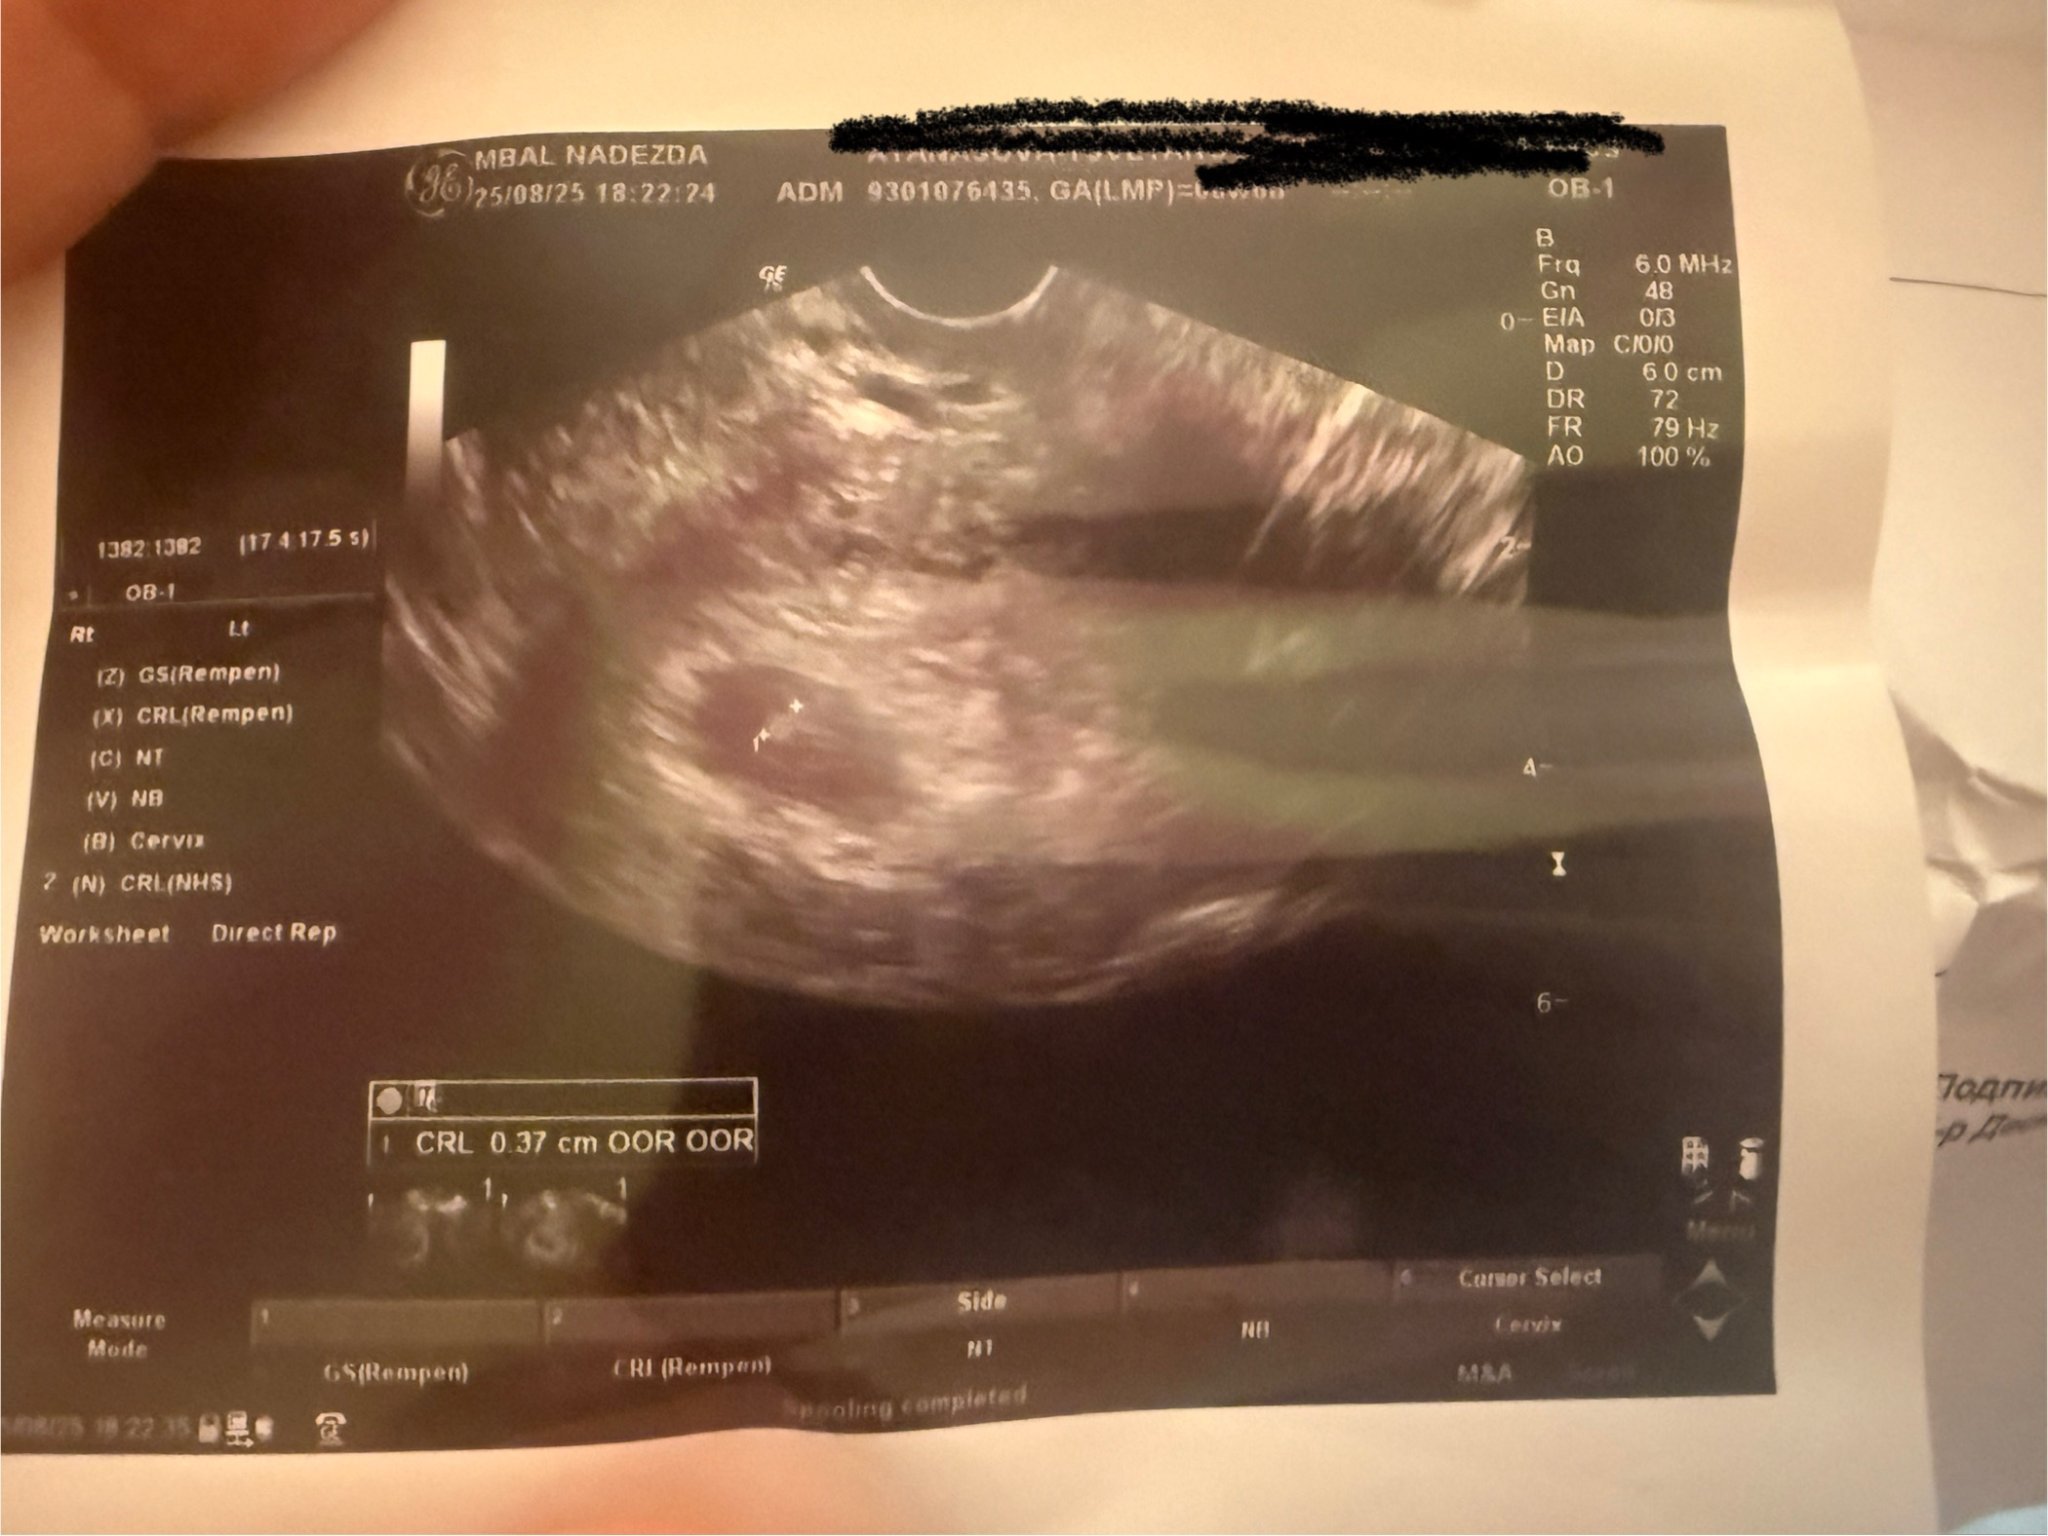

Това, което казва GA (LMP) е гестационната възраст според цикъла, но то е покрито. Идва от gestational age last menstrual period

Не виждам къде пише по размер колко е, може би и то е под черното

Извинявай, скрила съм си името. Иначе там на GA пише 6w6d (разбирам 6 седмици и 6 дни), което наистина е гестационната седмица по календар. Иначе размера е 3,7 милиметра.